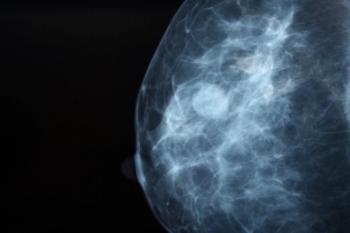

Despite advanced technology and new treatment breakthroughs in cancer care, treatment disparity remains among African American women with breast cancer.